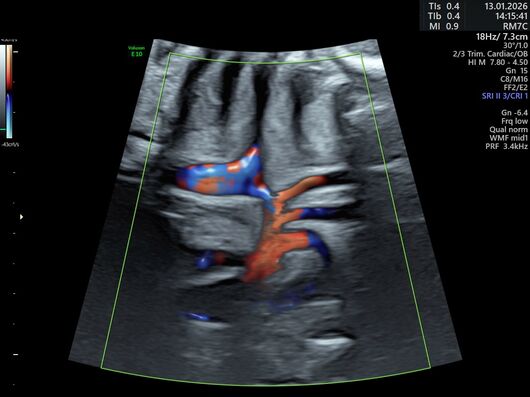

Für Diagnostik und Therapie stehen uns ein hochmodernes, kindergerechtes Herzkatheterlabor, ein hochauflösender strahlenarmer Photon-Counting-CT, MRT und moderne 3D-Ultraschallgeräte zur Verfügung. Die herzchirurgische Versorgung unserer Patientinnen und Patienten erfolgt durch die hochqualifizierten Operateure der Klinik für Kinderherzchirurgie und Chirurgie angeborener Herzfehler.